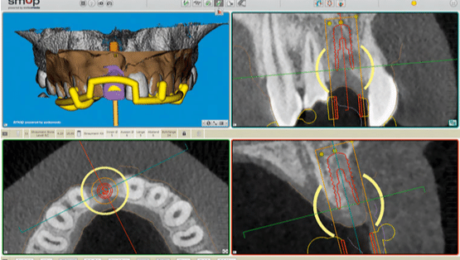

Un cone beam et une prise d’empreinte optique ont été nécessaire pour réaliser la planification implantaire du cas.

2 guides SMOP ont été imprimé, appuis dentaires, muqueux + fixation par clavettes.

Le guide SMOP est numérisé en place avec les transferts, cela nous permet de retrouver l’occlusion.